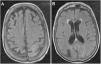

El síndrome de encefalopatía posterior reversible (PRES) constituye una entidad clínico-radiológica relacionada con múltiples etiologías con hallazgos similares en neuroimagen. Su incidencia es desconocida y su patogenia es multifactorial, englobando fenómenos de disfunción endotelial y autorregulación del flujo cerebral, entre otros. Existe una gran variedad de condiciones asociadas, siendo las más frecuentes la hipertensión, eclampsia y la terapia inmunosupresora, junto con otros fármacos, drogas, enfermedades autoinmunes e incluso la uremia.

Posterior reversible encephalopathy syndrome (PRES) is a clinical and radiological entity linked to multiple aetiologies with similar neuroimaging findings. Its incidence is unknown, and its pathogenesis is multifactorial, encompassing phenomena of endothelial dysfunction and cerebral flow autoregulation, inter alia. There is a wide variety of associated conditions, the most frequent being hypertension, eclampsia, and immunosuppressive therapy, along with other drugs, autoimmune diseases, and even uraemia.